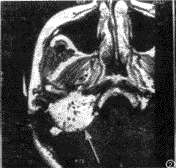

图1 右侧颈静脉球瘤,横轴位T1WI示右侧颈静脉孔区病灶呈等信号(黑箭),其内可见明显流空(箭头)